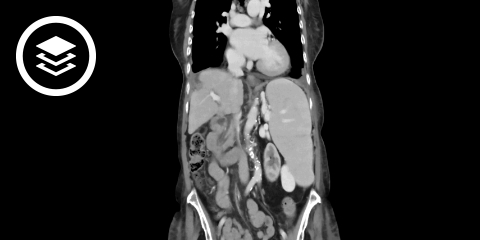

CT-Fallbeispiel

DICOM-Modelle können auf Mobilgeräten leider nicht angezeigt werden.

Die Diagnosesicherung erfolgt durch bildgebende Verfahren wie Sonographie, MRT oder CT. Dabei kann auch die Binnenstruktur der Milz analysiert werden, die weitere differentialdiagnostische Anhaltspunkte liefert.

- Bildquelle DICOM-Viewer: Datensatz freundlicherweise zur Verfügung gestellt durch die Klinik für diagnostische und interventionelle Radiologie, St. Vinzenz Hospital Köln